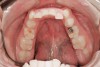

Figure 4  Indentations on tongue caused by forceful pressing of tongue on lingual surfaces. By pushing the tongue anteriorly, the airway is opened.

Figure 4

Bruxism and airway appear to be related to the patient's attempt to develop a patent airway during a desaturation episode. The majority of SB episodes occurs in a supine position and may be associated with either a reduction in the airway passage or increase in its resistance. During resumption of ventilation following apnea, a co-activation of both jaw-opening and jaw-closing muscles produce dilation of the upper airway. This permits a rise in inspiratory flow and reduces upper airway resistance.37 It has been reported that 99% of all rhythmic masticatory muscle activities were associated with a change in the respiratory amplitude and frequency.19 Changes in lateral tongue contours, long associated with nocturnal bruxers, can now be explained. The patient attempts to provide a patent airway by activating the tongue muscles and forcing the tongue off the airway and against the teeth (Figure 4).